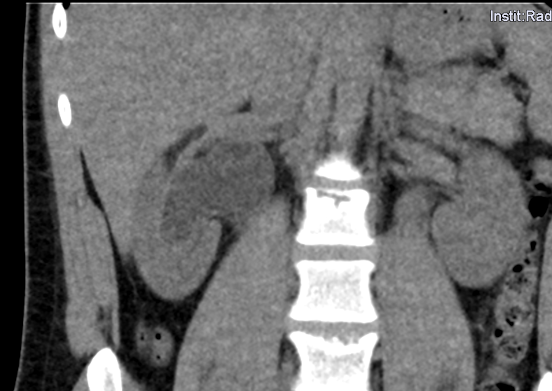

In diesem Fallbericht beschreiben wir einen 17-jährigen Patienten, der mit rez. ausgeprägten Koliken in unserer Abteilung vorstellig wurde. Initial erfolgte bei Hydronephrose °III und pos. Steinanamnese des Vaters eine CT-Abdomen nativ, welche bereits den V.a. einen retrocavalen Harnleiter rechts ergab. Eine Szintigraphie bestätigte eine urodynamisch relevante Obstruktion bei ausgeglichener Nierenfunktions. Bei Symptomatik erfolgte eine retrograde Ureteropyelographie mit JJ-Einlage. Im weiteren Verlauf wurde noch eine MRT-Angiographie durchgeführt, welche den Befund eindeutig bestätigte. Daraufhin erfolgte am 10.11.2025 die daVinci-assistierte Ureterureterostomie rechts in Linksseitenlage. Hierfür wurden 4 Arbeitstrokare und ein Kameratrokar verwendet. Die Gesamtoperationszeit lag bei 181 min, die reine Konsolenzeit bei ca. 100 min. Intraoperativ erfolgte ein JJ-Wechsel. Die Anastomose erfolgte mit einer 4.0 Quill-Naht in fortlaufender Technik. Der Blutverlust lag bei ca. 20 ml. Postoperativ waren die Schmerzen mit Novalgin gut beherrschbar. Die Entlassung erfolgte am 5. postoperativen Tag nach DK-Entfernung.